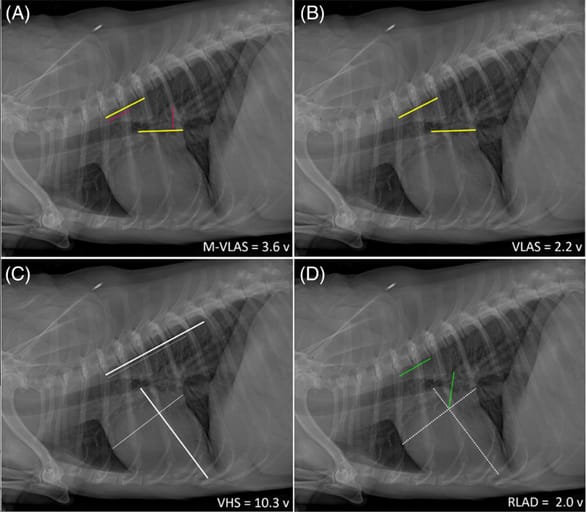

Measurements of M-VLAS, VLAS, VHS, and RLAD demonstrated on the same right lateral inspiratory radiograph of a dog with stage B2 MMVD. All methods take their respective measurements from the cranial edge of the T4 vertebral body extending caudally, parallel to the vertebral column, rounded to the nearest 0.1 vertebrae. A. MVLAS—an initial line (yellow)—is drawn from the centre of the most ventral aspect of the carina to the intersection between the most caudal aspect of the left atrium and the dorsal border of the caudal vena cava. A second additional line (red) is then drawn from the most distal border of the left atrium towards the first line, intersecting it perpendicularly. Two separate straight lines corresponding to the lengths of the first 2 lines (yellow + red) were then drawn from the cranial edge of the T4 vertebral body extending in a caudal direction, ventral and parallel to the vertebral canal. The M-VLAS for this dog is 2.2 + 1.4 = 3.6 vertebrae (v). (Note: the first value being the VLAS.) B. Vertebral left atrial size (VLAS = 2.2v)—yellow line C. Vertebral heart score (VHS = 5.7 + 4.6 = 10.3v), vertical axis—thick white line; horizontal axis—thin white line. D. Radiographic left atrial dimension (RLAD = 2.0v)—dashed white lines represent the VHS vertical and horizontal axes, constituting the foundation for the RLAD measurement (green line), which bisects the VHS intersection.